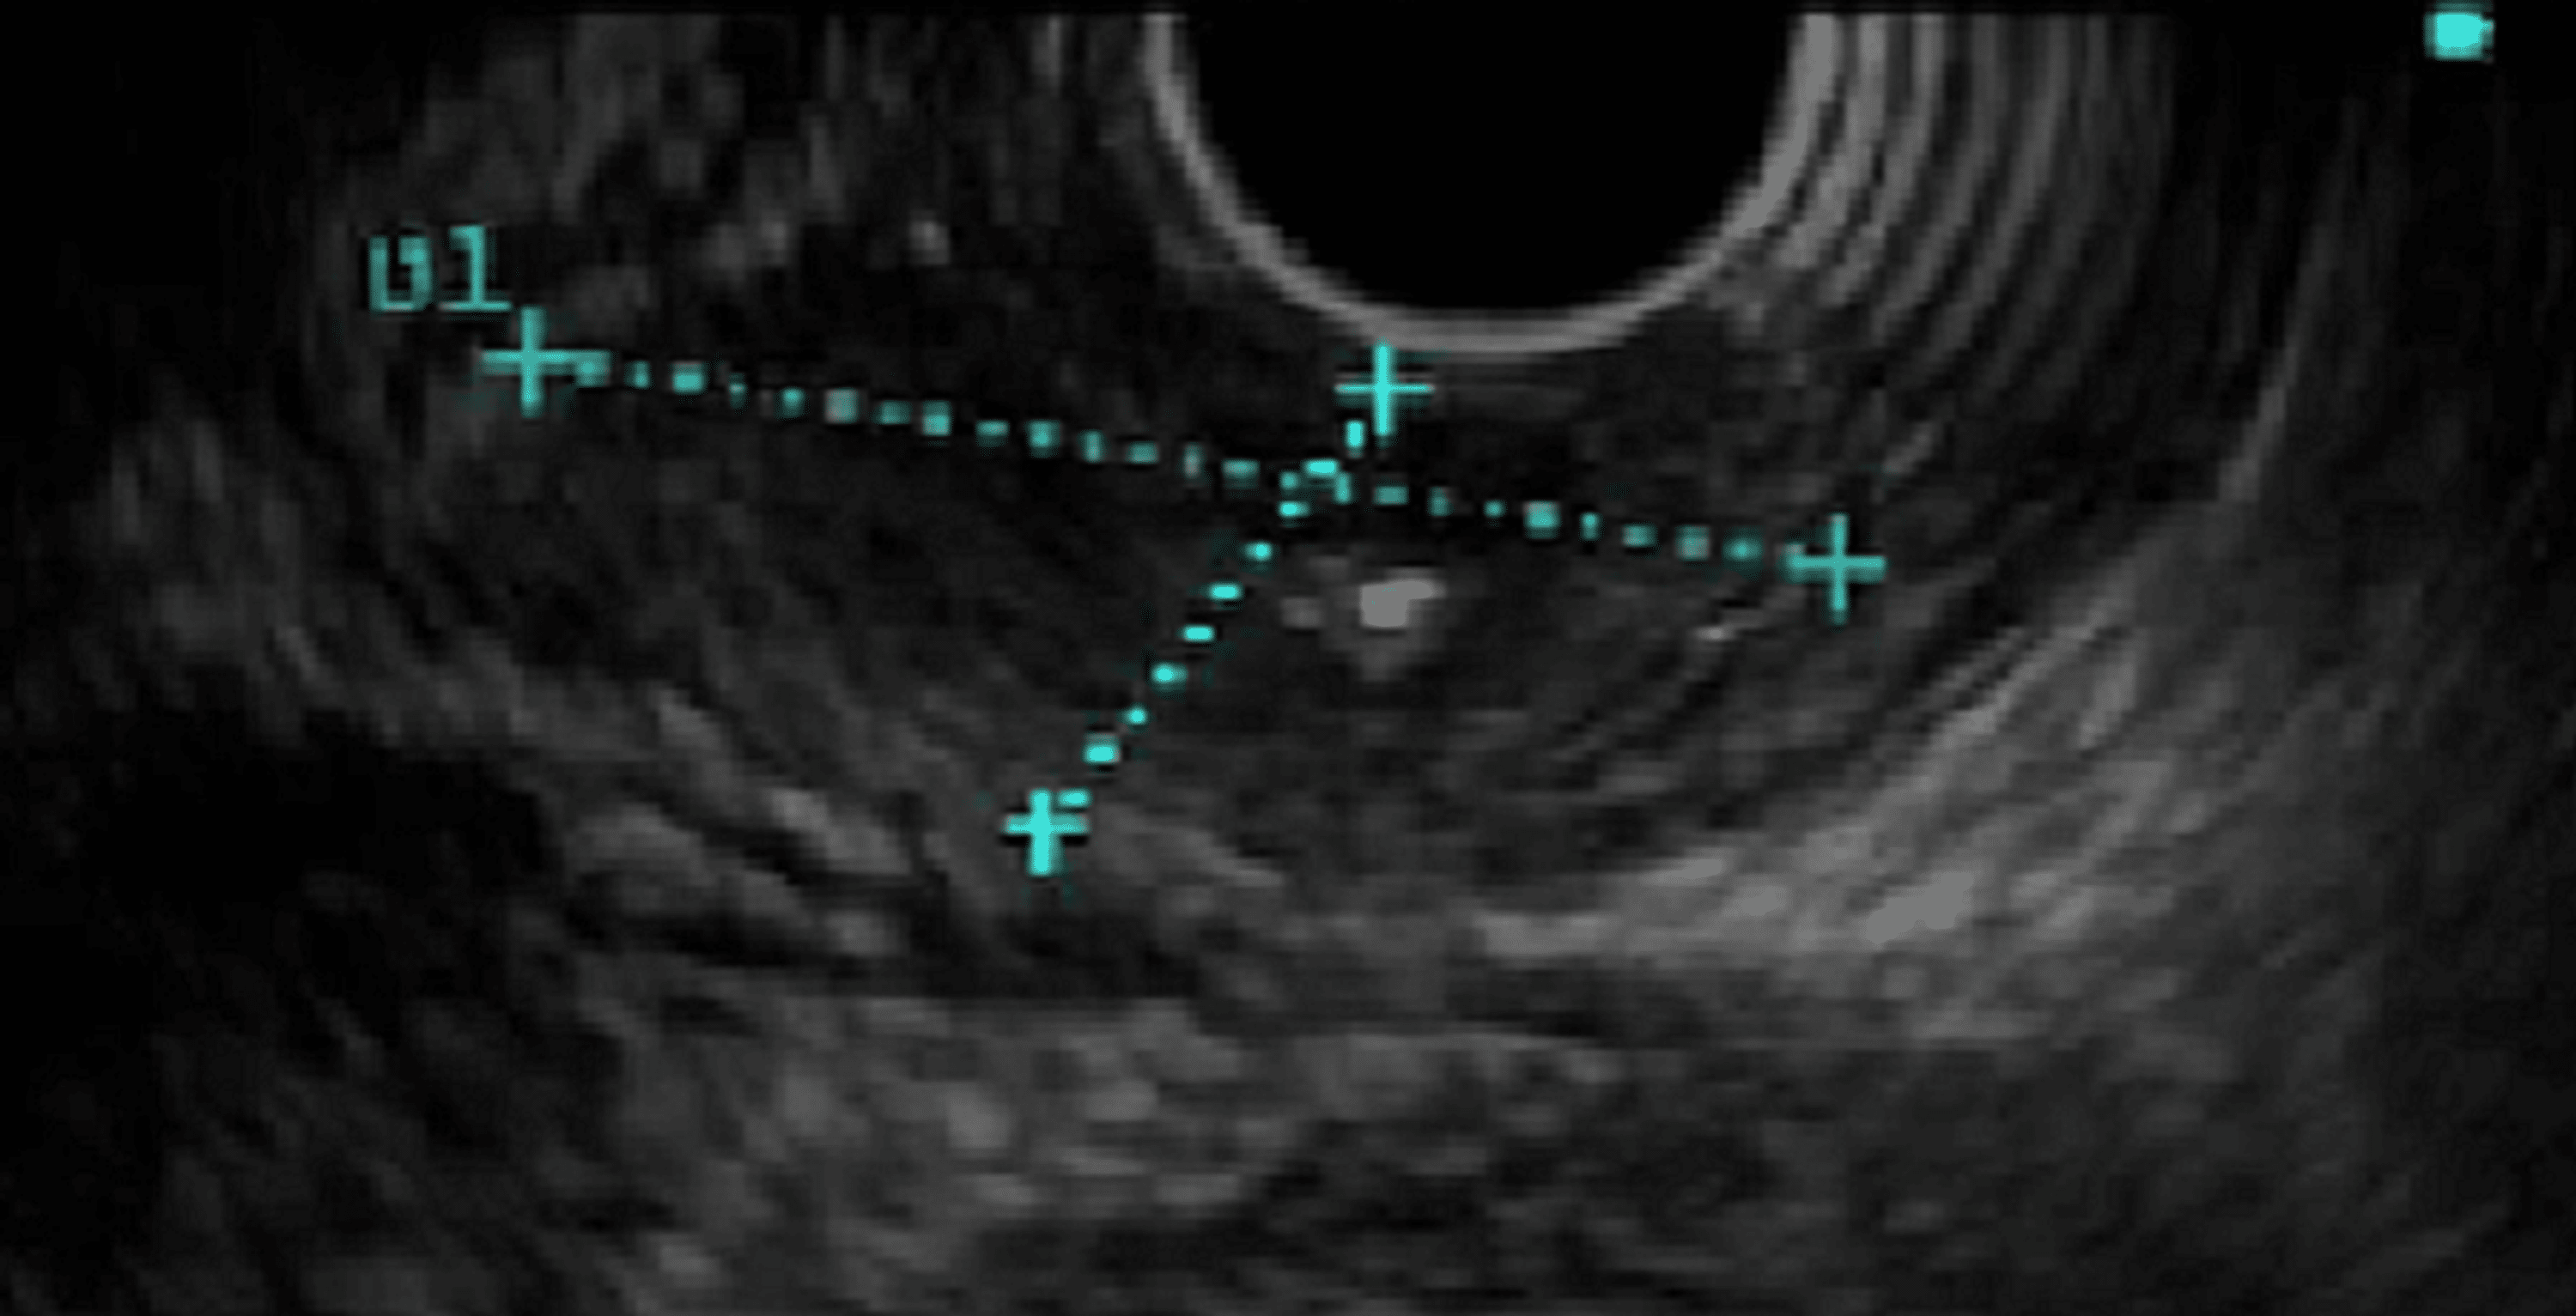

From www.semanticscholar.org

Figure 3 from A Case of Endoscopically Complete Remission of Esophageal Neuroendocrine Cancer Esophagus esophageal neuroendocrine tumors (nets) are rare, aggressive and lacking specific symptoms. the clinicopathological features and optimum treatment of esophageal neuroendocrine carcinoma. neuroendocrine carcinomas (necs) of the esophagus are extremely rare and poorly understood. to collect the cells, the doctor might insert a long, thin tube with a light and a camera on the end into your. Neuroendocrine Cancer Esophagus.